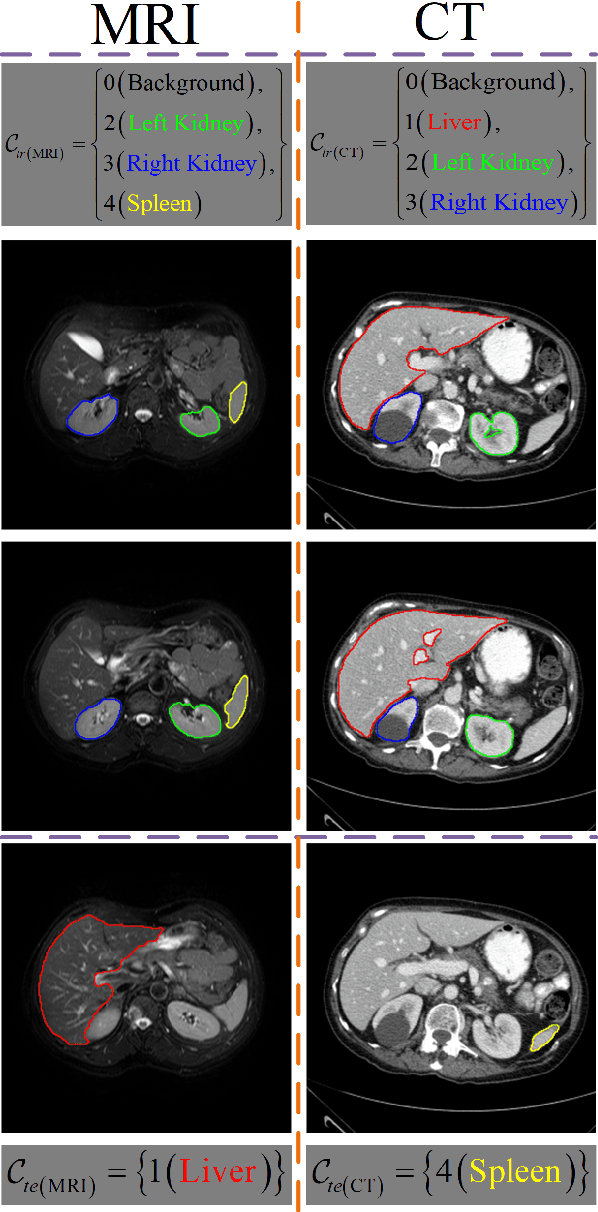

Abstract:Despite deep convolutional neural networks achieved impressive progress in medical image computing and analysis, its paradigm of supervised learning demands a large number of annotations for training to avoid overfitting and achieving promising results. In clinical practices, massive semantic annotations are difficult to acquire in some conditions where specialized biomedical expert knowledge is required, and it is also a common condition where only few annotated classes are available. In this work, we proposed a novel method for few-shot medical image segmentation, which enables a segmentation model to fast generalize to an unseen class with few training images. We construct our few-shot image segmentor using a deep convolutional network trained episodically. Motivated by the spatial consistency and regularity in medical images, we developed an efficient global correlation module to capture the correlation between a support and query image and incorporate it into the deep network called global correlation network. Moreover, we enhance discriminability of deep embedding to encourage clustering of the feature domains of the same class while keep the feature domains of different organs far apart. Ablation Study proved the effectiveness of the proposed global correlation module and discriminative embedding loss. Extensive experiments on anatomical abdomen images on both CT and MRI modalities are performed to demonstrate the state-of-the-art performance of our proposed model.